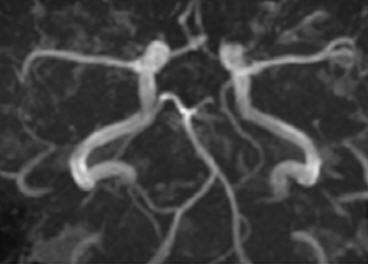

Imágenes de vasos sanguíneos en el cerebro. Los cambios en el flujo sanguíneo se pueden medir y sirven como índice de actividad neuronal.

Cuando la actividad neuronal aumenta se induce un aumento del movimiento de iones que a su vez activan las bombas iónicas que requieren energía, por lo que aparece un aumento del metabolismo energético y del consumo de oxígeno. Todo esto implica un aumento de deoxihemoglobina y una disminución de la señal magnética. Sin embargo, el aumento en el consumo de oxígeno va inmediatamente seguido (segundos) por un aumento local del flujo cerebral.

El aumento del flujo cerebral es mayor que el aumento en consumo de oxigeno; por lo tanto, hay un aumento relativo de oxihemoglobina y de intensidad de la señal. El mecanismo exacto de cómo se produce este aumento de flujo sanguíneo no está claro, pero parece ser que las responsables serian ciertas señales relacionadas con neurotransmisores.